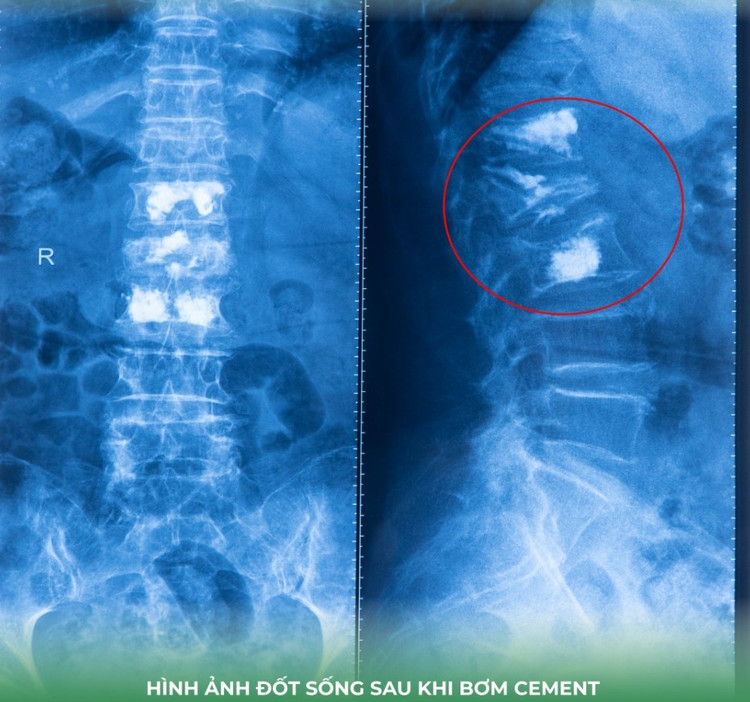

Sau khi hội chẩn, các bác sĩ quyết định điều trị giảm đau cột sống bằng phương pháp tạo hình thân đốt sống bằng bơm cement sinh học giúp cố định thân đốt sống bị xẹp, cải thiện tình trạng giảm đau nhức, phục hồi vận động sớm và hạn chế biến chứng do nằm lâu, đặc biệt phù hợp với người cao tuổi.

xep-dot-song-2.jpg